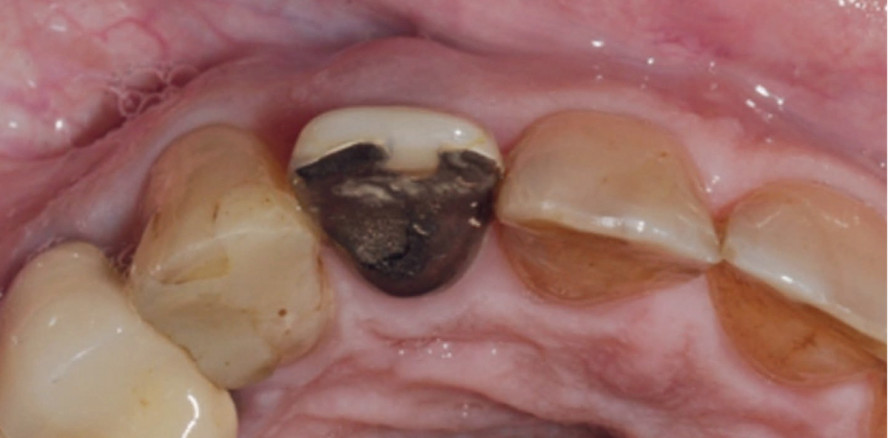

Abb. 1a–c: Die klinische Ausgangssituation mit nicht erhaltungswürdigem Zahn 12 bei Längsfraktur. © Univ.-Prof. Dr. Dr. Bilal Al-Nawas, Priv.-Doz. Dr. med. Dr. med. dent. Keyvan Sagheb, Dr. Stefan Wentaschek, Dr. med. dent. Yasamin Habibi